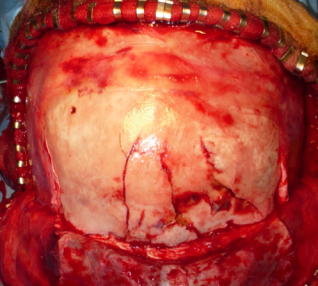

- taille d’un volet fronto-basal centré sur le ptérion et dépassant largement la ligne médiane pour exposer le toît d’orbite des deux côtés

- cranialisation du sinus frontal

- suspension périphérique et ouverture durale parabasale « en sourcils »

- exploration sous microscope du toît orbitaire et des goutières olfactives, en arrière jusqu’aux canaux optiques et au planum

- identification de la brèche ostéo-durale : souvent le cerveau fait hernie, une artériole corticale saigne au décollement ; exposition des limites du défect

- fermeture par suture primaire parfois (déchirure linéaire antéro-postérieure), plus souvent plastie par patch de périoste prélevé en arrière de l’incision du scalp, suturé par surjet de prolène, avec application de colle de fibrine